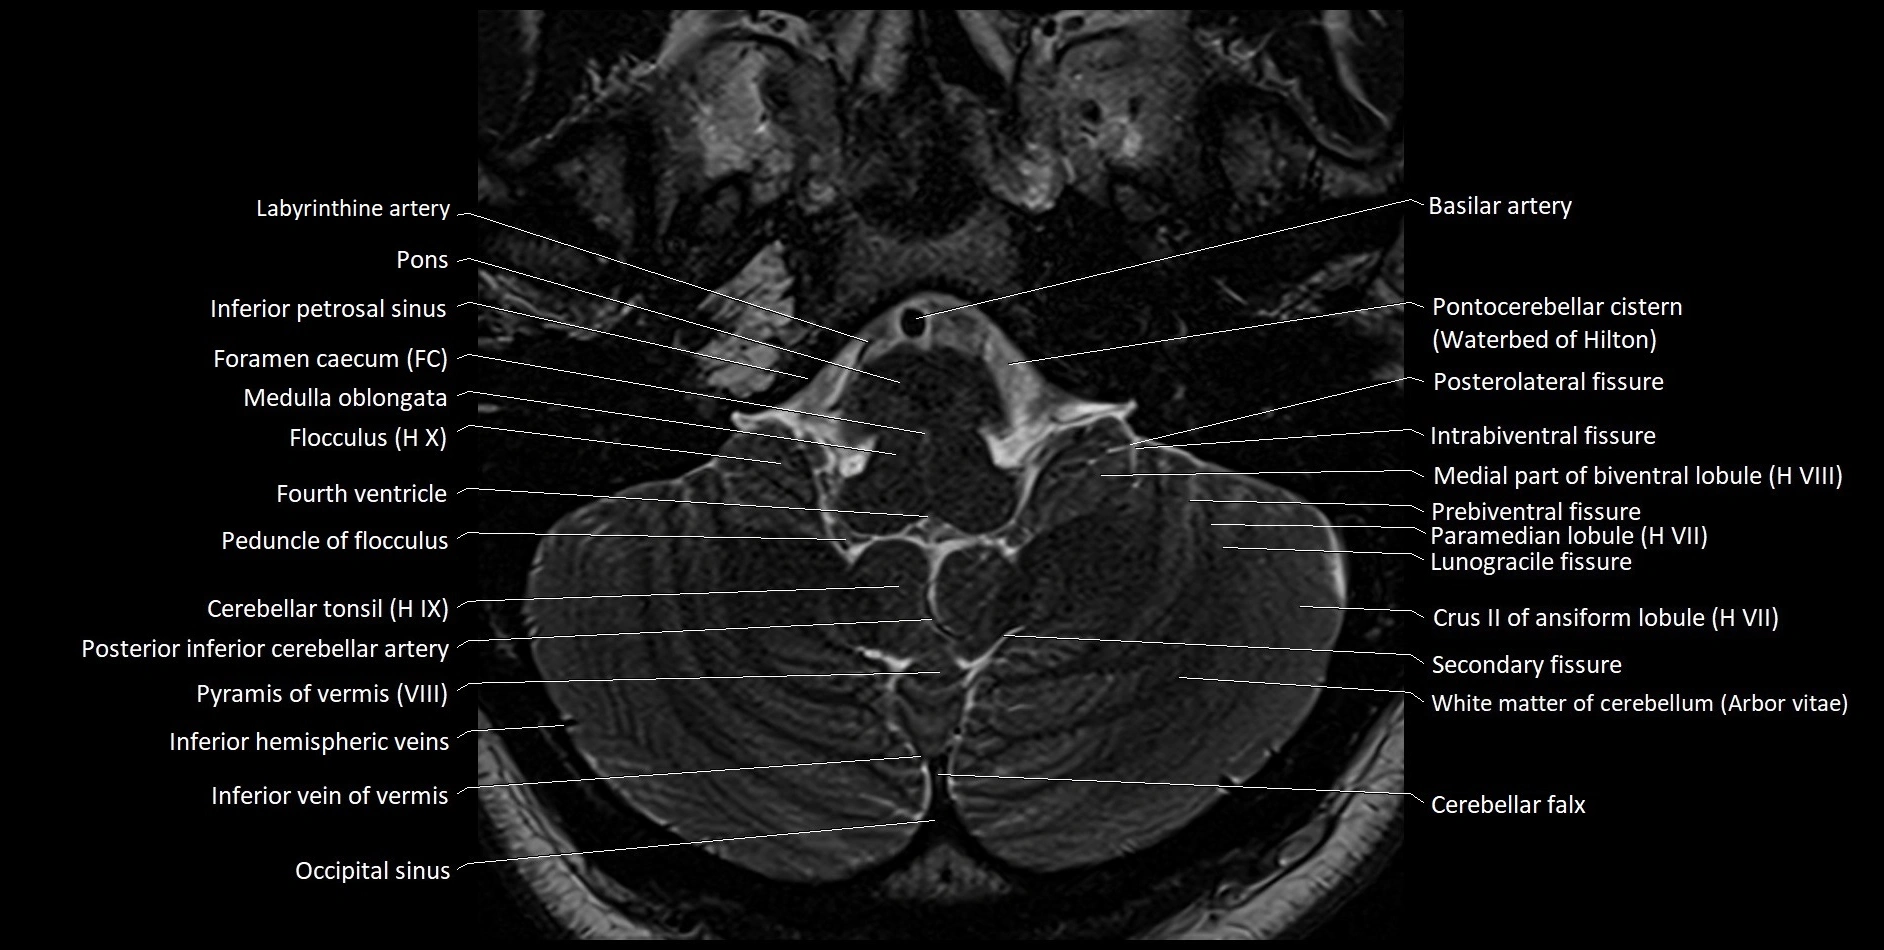

- Flocculus

- Peduncle of flocculus

- Cerebellar tonsil (H IX)

- Posterior inferior cerebellar artery

- Pyramid of vermis (VIII)

- Inferior hemispheric veins of the cerebellum

- Inferior vein of vermis

- Occipital sinus

- Crus II of ansiform lobule of cerebellum

- Paramedian lobule (HVII) of cerebellum

- Intrabiventral Fissure of Biventral Lobule

- Medial part of biventeral lobule

- Prebiventral fissure

- Lunogracle fissure

- Cerebellar falx

- Inferior petrosal sinus